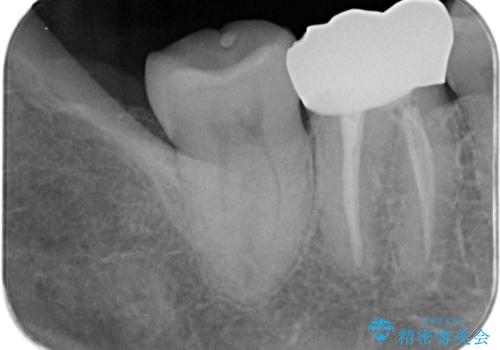

- 冷たいもので長引く痛みがあることを主訴に来院されました。

抜髄を行い、オールセラミッククラウンにて修復を行いました。

根管充填はバイオセラミックシーラーを使用しています。